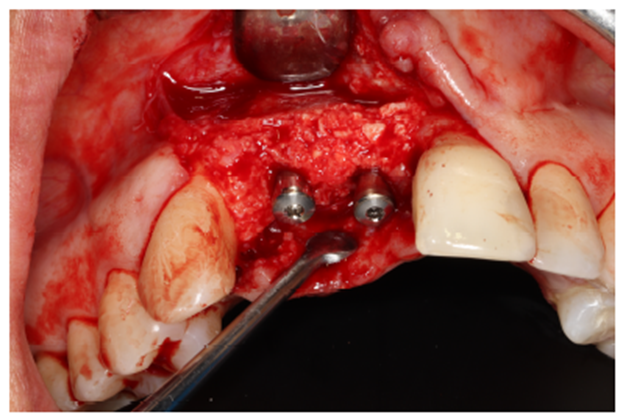

O material de enxerto ósseo particulado (Bio-Oss) foi preparado junto com as membranas de fibrina autógenas (L-PRF). O mesmo foi levado e acomodado no arcabouço entre as membranas e o osso descorticalizado. É de suma importância que toda a região que, posteriormente, receberá um implante dentário seja totalmente recoberta pelo material de enxerto e as membranas de PTFE-d, para que não ocorram GAPS que impossibilitariam uma futura reabilitação. (Figuras 6.1 e 7.1).

Após a estabilização do enxerto ósseo é recomendável a retenção vestibular das membranas com parafusos de fixação. É importante manter o sítio cirúrgico sem grandes pressões ou movimentações, respeitando os princípios básicos para o sucesso do enxerto, evitando a formação de fibrose. A escolha do parafuso depende da habilidade e preferência do cirurgião. Deve-se sempre ter em mesa o kit de chaves ideal como o parafuso de fixação de escolha. Neste caso, utilizou-se os parafusos de 12 mm de altura da Maximus.Vale ressaltar que o reforço de titânio viabiliza uma manipulação clinica facilitada e auxilia na proteção do enxerto frente às movimentações e/ou pressões (Figura 8).